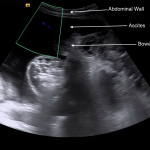

ABDOMINAL ULTRASOUND

Key features of ascites seen in this imaging modality are:

- Anechoic nature: ascites will allow sound waves to pass through it, so it will appear black/dark on ultrasound.

The gallery below organizes examples of how ascites will appear on abdominal ultrasound. Click on the thumbnails below to open up the gallery: